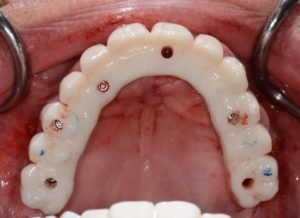

Juste après la pose des implants, prise d’empreinte numérique à l’aide des transferts digitaux.

Le guide SMOP est numérisé en place avec les transferts, cela nous permet de retrouver l’occlusion.

La réalisation des 2 bridges transvissés provisoires peut commencer sur le logiciel Exocad.